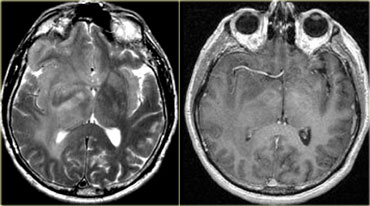

Melanoma metastasis: T2WI and T1WI Melanoma metastasis: T2WI and T1WI

Intra- vs Extra-axial (2)

The differentiation between intra-axial versus extra-axial is usually straight forward, but sometimes it can be very difficult and imaging in multiple planes may be necessary.

The tumor in the case on the left was thought to be a falcine meningioma, i.e. extra-axial and was presented for surgery.

This lesion surely has the appearance of a meningioma: these tumors can be hypointense on T2 due to a fibrocollageneous matrix or calcifications and frequently produce reactive edema in the adjacent white matter of the brain.

However, there is gray matter on the anteromedial and posteromedial side of the lesion (red arrow).

This indicates that the lesion is intra-axial.

If the lesion was extra-axial the gray matter should have been pushed away.

This proved to be a melanoma metastasis.